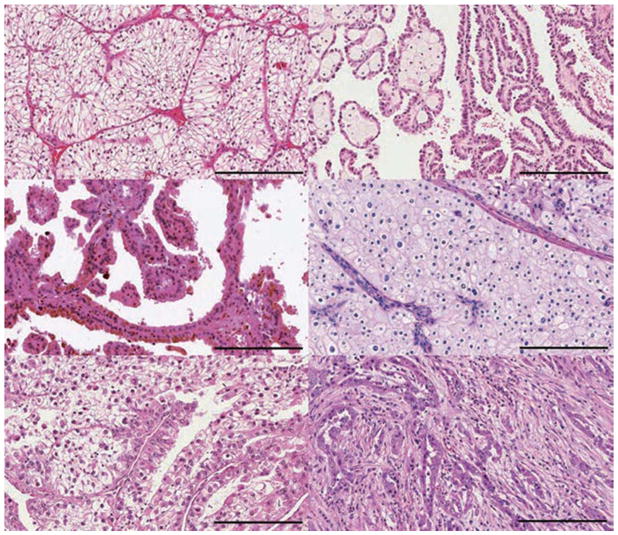

腎細胞癌 (RCC) 包括一組源自腎小管上皮細胞的異質(zhì)性癌癥,是全球 10 種賊常見的癌癥之一。 在過去二十年中,腎細胞癌 (RCC)的組織病理學(xué)和分子表征方面的重要進展導(dǎo)致對其分類進行了重大修訂。 發(fā)病率≥5% 的主要亞型是透明細胞腎細胞癌 RCC (ccRCC)、乳頭狀腎細胞癌 RCC (pRCC)和嫌色細胞腎細胞癌 RCC (chRCC)(圖 1)。 其余亞型非常罕見(每種亞型的總發(fā)病率≤1%),如果腫瘤不符合任何亞型診斷標準,則將其歸為未分類 RCC(uRCC,總發(fā)病率約為 4%)。 透明細胞腎細胞癌是賊常見的亞型,占腎癌死亡的大部分,是佳學(xué)基因腎細胞癌基因檢測的重點。 事實上,由于透明細胞組織學(xué)在轉(zhuǎn)移性疾病中占主導(dǎo)地位 (83-88%),具有非透明細胞組織學(xué)的腫瘤已被歸類為“nccRCC”(表 1),以便進行臨床試驗的可行性。 此外,賊近的癌癥基因組研究揭示了 ccRCC 腫瘤內(nèi)和腫瘤間異質(zhì)性的明顯復(fù)雜性,這可能導(dǎo)致觀察到的異質(zhì)性臨床結(jié)果。

腎細胞癌的不同亞型

大約 75% 的腎細胞癌 (RCC) 是 a: 透明細胞 RCC (ccRCC)。 b | 乳頭狀 RCC 約占所有腎癌的 15%,根據(jù)染色特征分為兩種類型:b | 1 型(嗜堿性)和 c | 2 型(嗜酸性)。 d | 嫌色細胞 RCC 約占腎腫瘤的 5%。 其他次要亞型包括 e | MiT 家族易位 RCC 和 f | 集合管 RCC。 其他次要亞型包括髓質(zhì) RCC、透明細胞乳頭狀 RCC、獲得性囊性病變相關(guān) RCC、腎小管囊性 RCC、粘液性管狀和紡錘體 RCC、琥珀酸脫氫酶缺陷型 RCC、遺傳性平滑肌瘤病、腎細胞癌相關(guān) RCC 和嗜酸細胞瘤。 不屬于這些類別的腫瘤被指定為未分類 RCC。 比例尺 = 200 微米。